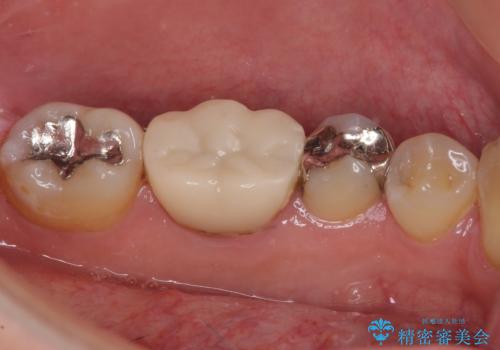

- 保険診療で装着した奥歯の白いクラウンの具合がよくないとのことで来院された患者様です。

保険診療で安価に白いクラウンが入れられるということで選択されたそうですが、装着後に痛みを感じたり、ものが挟まって不快であったりと不便が多いため、セラミッククラウンにて補綴治療を行うこととしました。

保険診療では、安価に白いクラウンを装着できる代償として、歯とクラウンの境目が不適合であったり、歯と歯の間にものが挟まりやすかったりと、不快な思いをされることがしばしばあります。

自費診療は、費用が高くなりますが、よい材料を選択したり、診療時間を十分にとったりできるため、単純に白いだけではない、良質なクラウンを装着することが可能です。